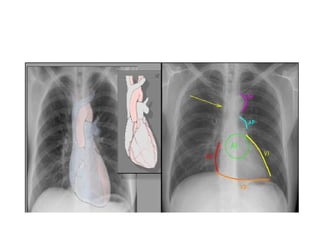

• Después de una visión global de la

radiografía de tórax, es aconsejable

efectuar un análisis sistemático en el que se

tomen en cuenta:

• El análisis del marco óseo y las partes

blandas, incluyendo los rebordes costales y

senos costofrénicos.

• La valoración del volumen respectivo de

cada uno de los pulmones.

• El análisis de la silueta cardíaca, en el que

se valoren el tamaño, forma, así como los

elementos característicos del borde de la

• Después deuna visión global de la radiografía de tórax, es aconsejable efectuar un análisis sistemático en el que se tomen en cuenta: • El análisis del marco óseo y las partes blandas, incluyendo los rebordes costales y senos costofrénicos. • La valoración del volumen respectivo de cada uno de los pulmones. • El análisis de la silueta cardíaca, en el que se valoren el tamaño, forma, así como los elementos característicos del borde de la